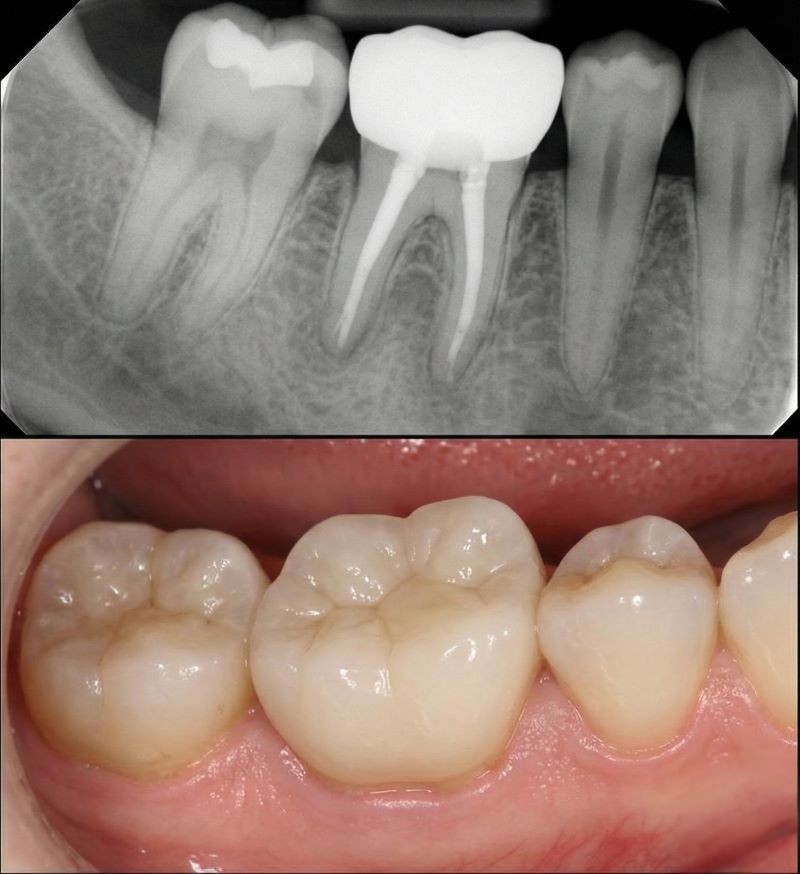

Root canal therapy is an endodontic procedure that removes diseased or inflamed pulp, disinfects the canals and seals them with gutta‑percha. After the canals are cleaned, the tooth is rebuilt with a filling or crown for strength and function. We offer retreatment root canals when previous therapy fails, a pulpotomy to partially remove the nerve in developing teeth and an apicoectomy (endodontic surgery) to remove infection at the root tip.

This treatment is recommended when deep decay, cracks, repeated dental work or trauma have inflamed the nerve. Preserving your natural tooth helps maintain your bite and jawbone better than extraction and implants. With modern anaesthetics and sedation, most patients feel little more than pressure. Techniques such as nickel-titanium files, ultrasonic irrigation and 3-D imaging allow precise and controlled treatment. A crowned, root-canal-treated tooth can last for decades with good oral hygiene.

Digital 3‑D imaging, rotary instruments and ultrasonic irrigation help us clean canals thoroughly and perform efficient single‑visit treatments.